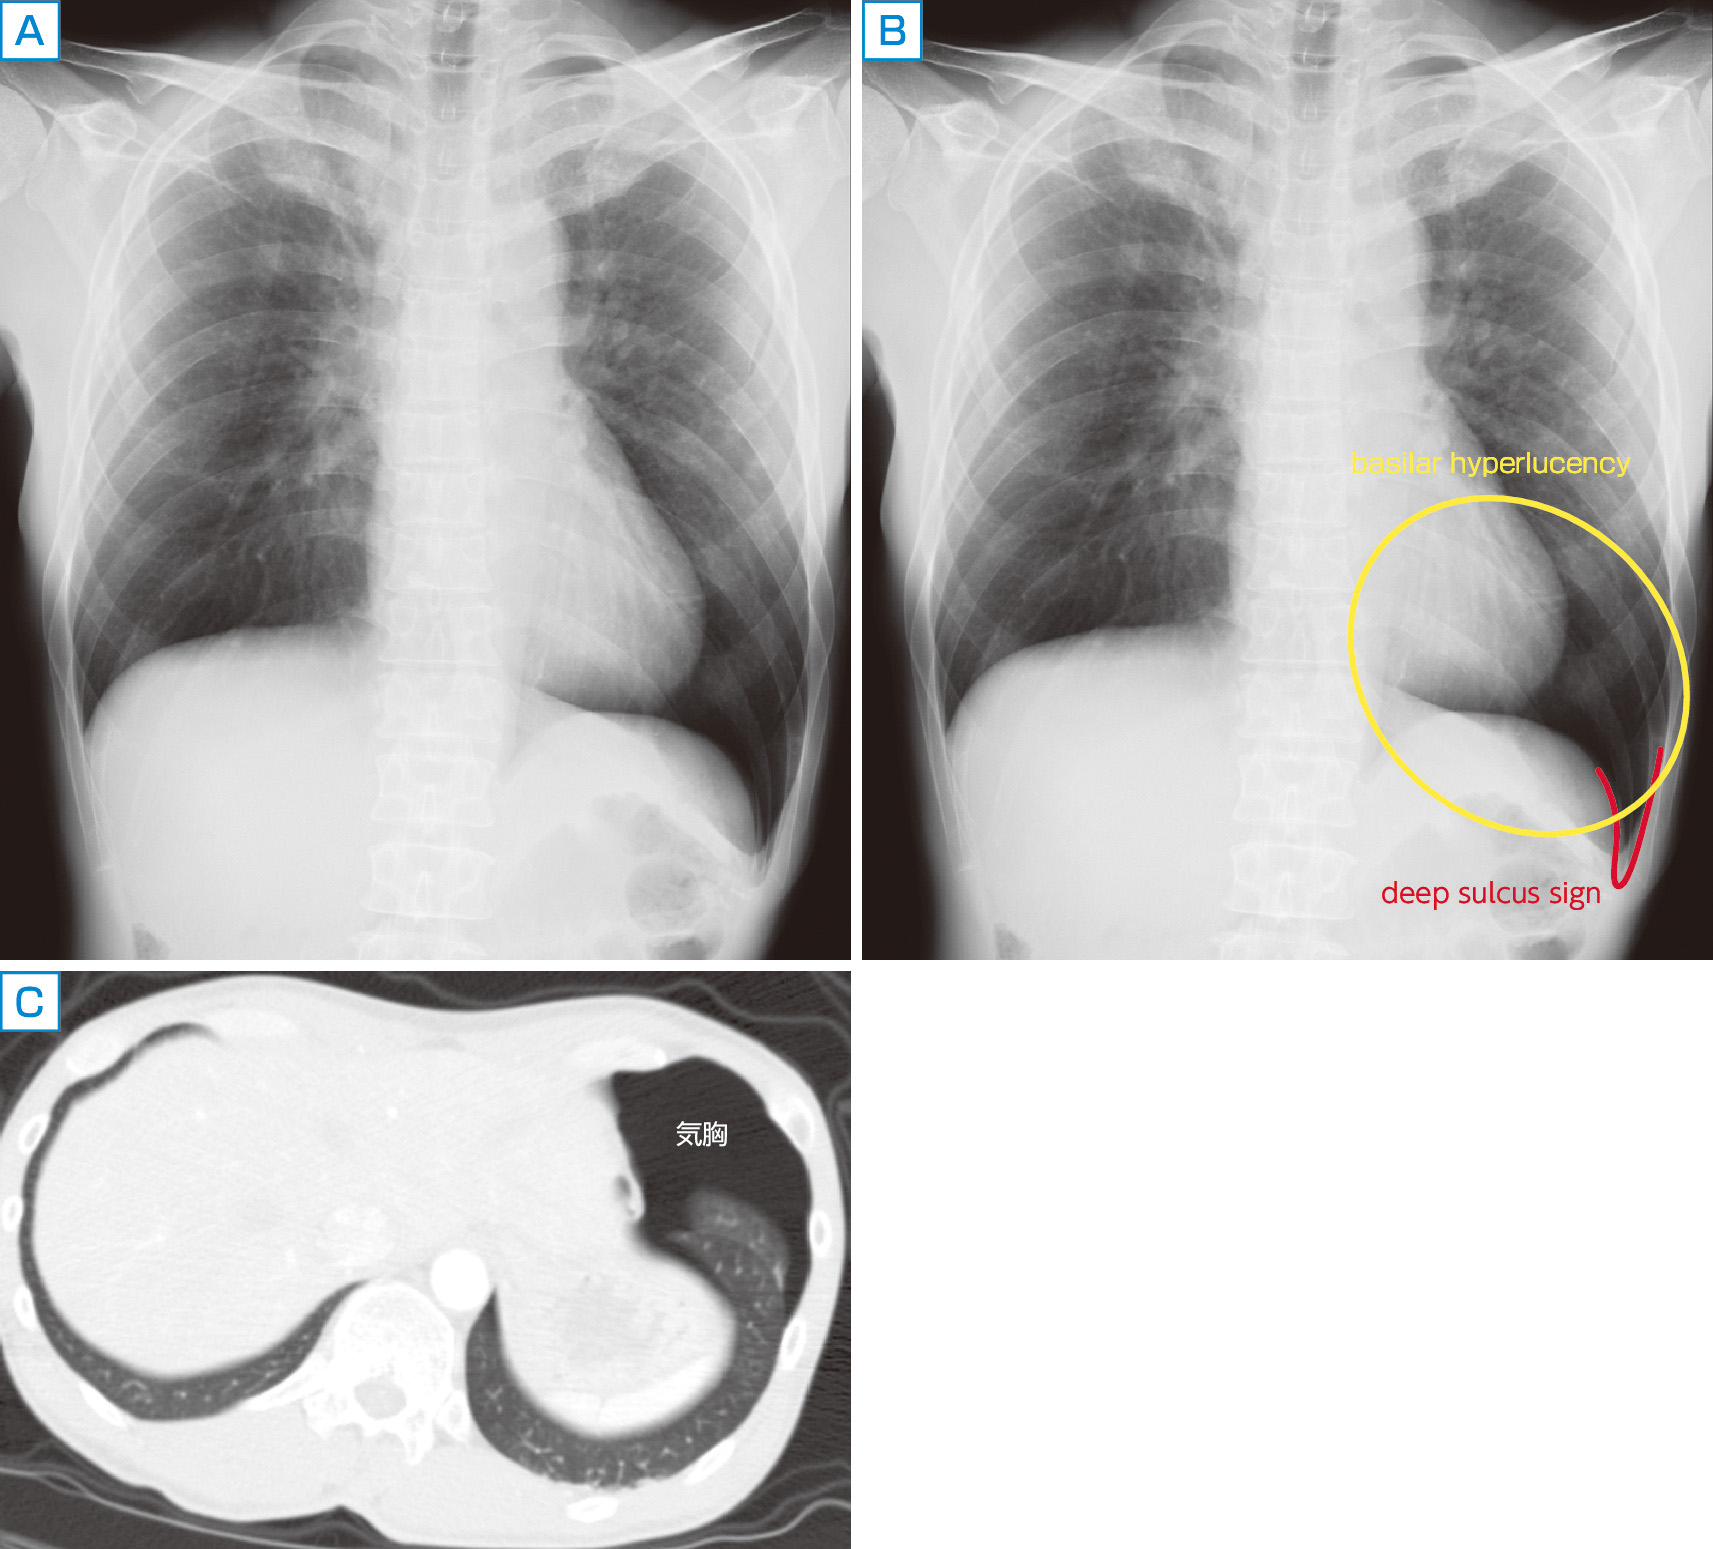

右第4肋骨に骨折がある.その他,大きな所見はないだろうか (A).左の肋骨横隔膜角が深く,左横隔膜の辺りが対側より黒くみえることに注目したい.これはそれぞれdeep sulcus sign,basilar hyperlucencyと呼ばれるサインであり臥位の胸部単純写真における気胸を示している (B).参考までに同症例のCT像を示す (C).臥位における気胸は立位に比べて気づくのが難しく,気胸を示唆するサインがないか普段から気をつけて読影するようにしたい.

また心左縁や左の横隔膜の輪郭が通常より明瞭であることに気づかれるだろうか.これは気胸の空気が心や横隔膜と直接接しているためである.無気肺や肺炎に接する心大血管の辺縁が不明瞭になる現象 (シルエットサイン) は有名であるが,本症例のように逆に通常より辺縁が明瞭にみえる場合には,気胸や縦隔気腫を疑ってみる.